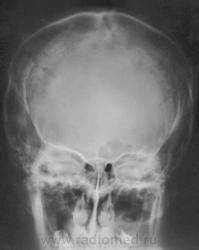

Nela. КТ головного мозга и костей. Гистиоцитоз Х (морфологическая верификация).

Пациент - молодой человек, предъявляет жалобы на головные боли и боли в шее. Болеет с 2002 года.

Гистиоцитоз Х – заболевание ретикулоцитарной системы неизвестной этиологии, морфологически характеризующееся первичной пролиферацией своеобразных гистиоцитов (клеток Лангерганса или клеток Х) и образованием в легких и в других органах и тканях гистиоцитарных гранулем и гранулематозных инфильтратов.

В понятие “гистиоцитоз Х” включают болезнь Abt–Letter–Siwe, болезнь Hand–Schuller–Christian, а также эозинофильную гранулему с разной степенью выраженности гистиоцитарной пролиферации.

Заболевание относится к системным: гранулемы могут образовываться в различных органах, но наиболее часто поражаются легкие и кости. Заболевают чаще всего люди молодого возраста, между 20 и 40 годами, большей частьюмужчины.

Конечно чаще, но не каждый день. Гистиоцитоз Х или эозинофильная гранулема, или гистиоцитоз из клеток Лангерганса редкое заболевание. Но, думаю, каждый рентгенолог со стажем видел костный гистиоцитоз в костях свода или в позвонке. У нас областное гематологическое отделение, поэтому наверно раз в 1-2 года встречаем.